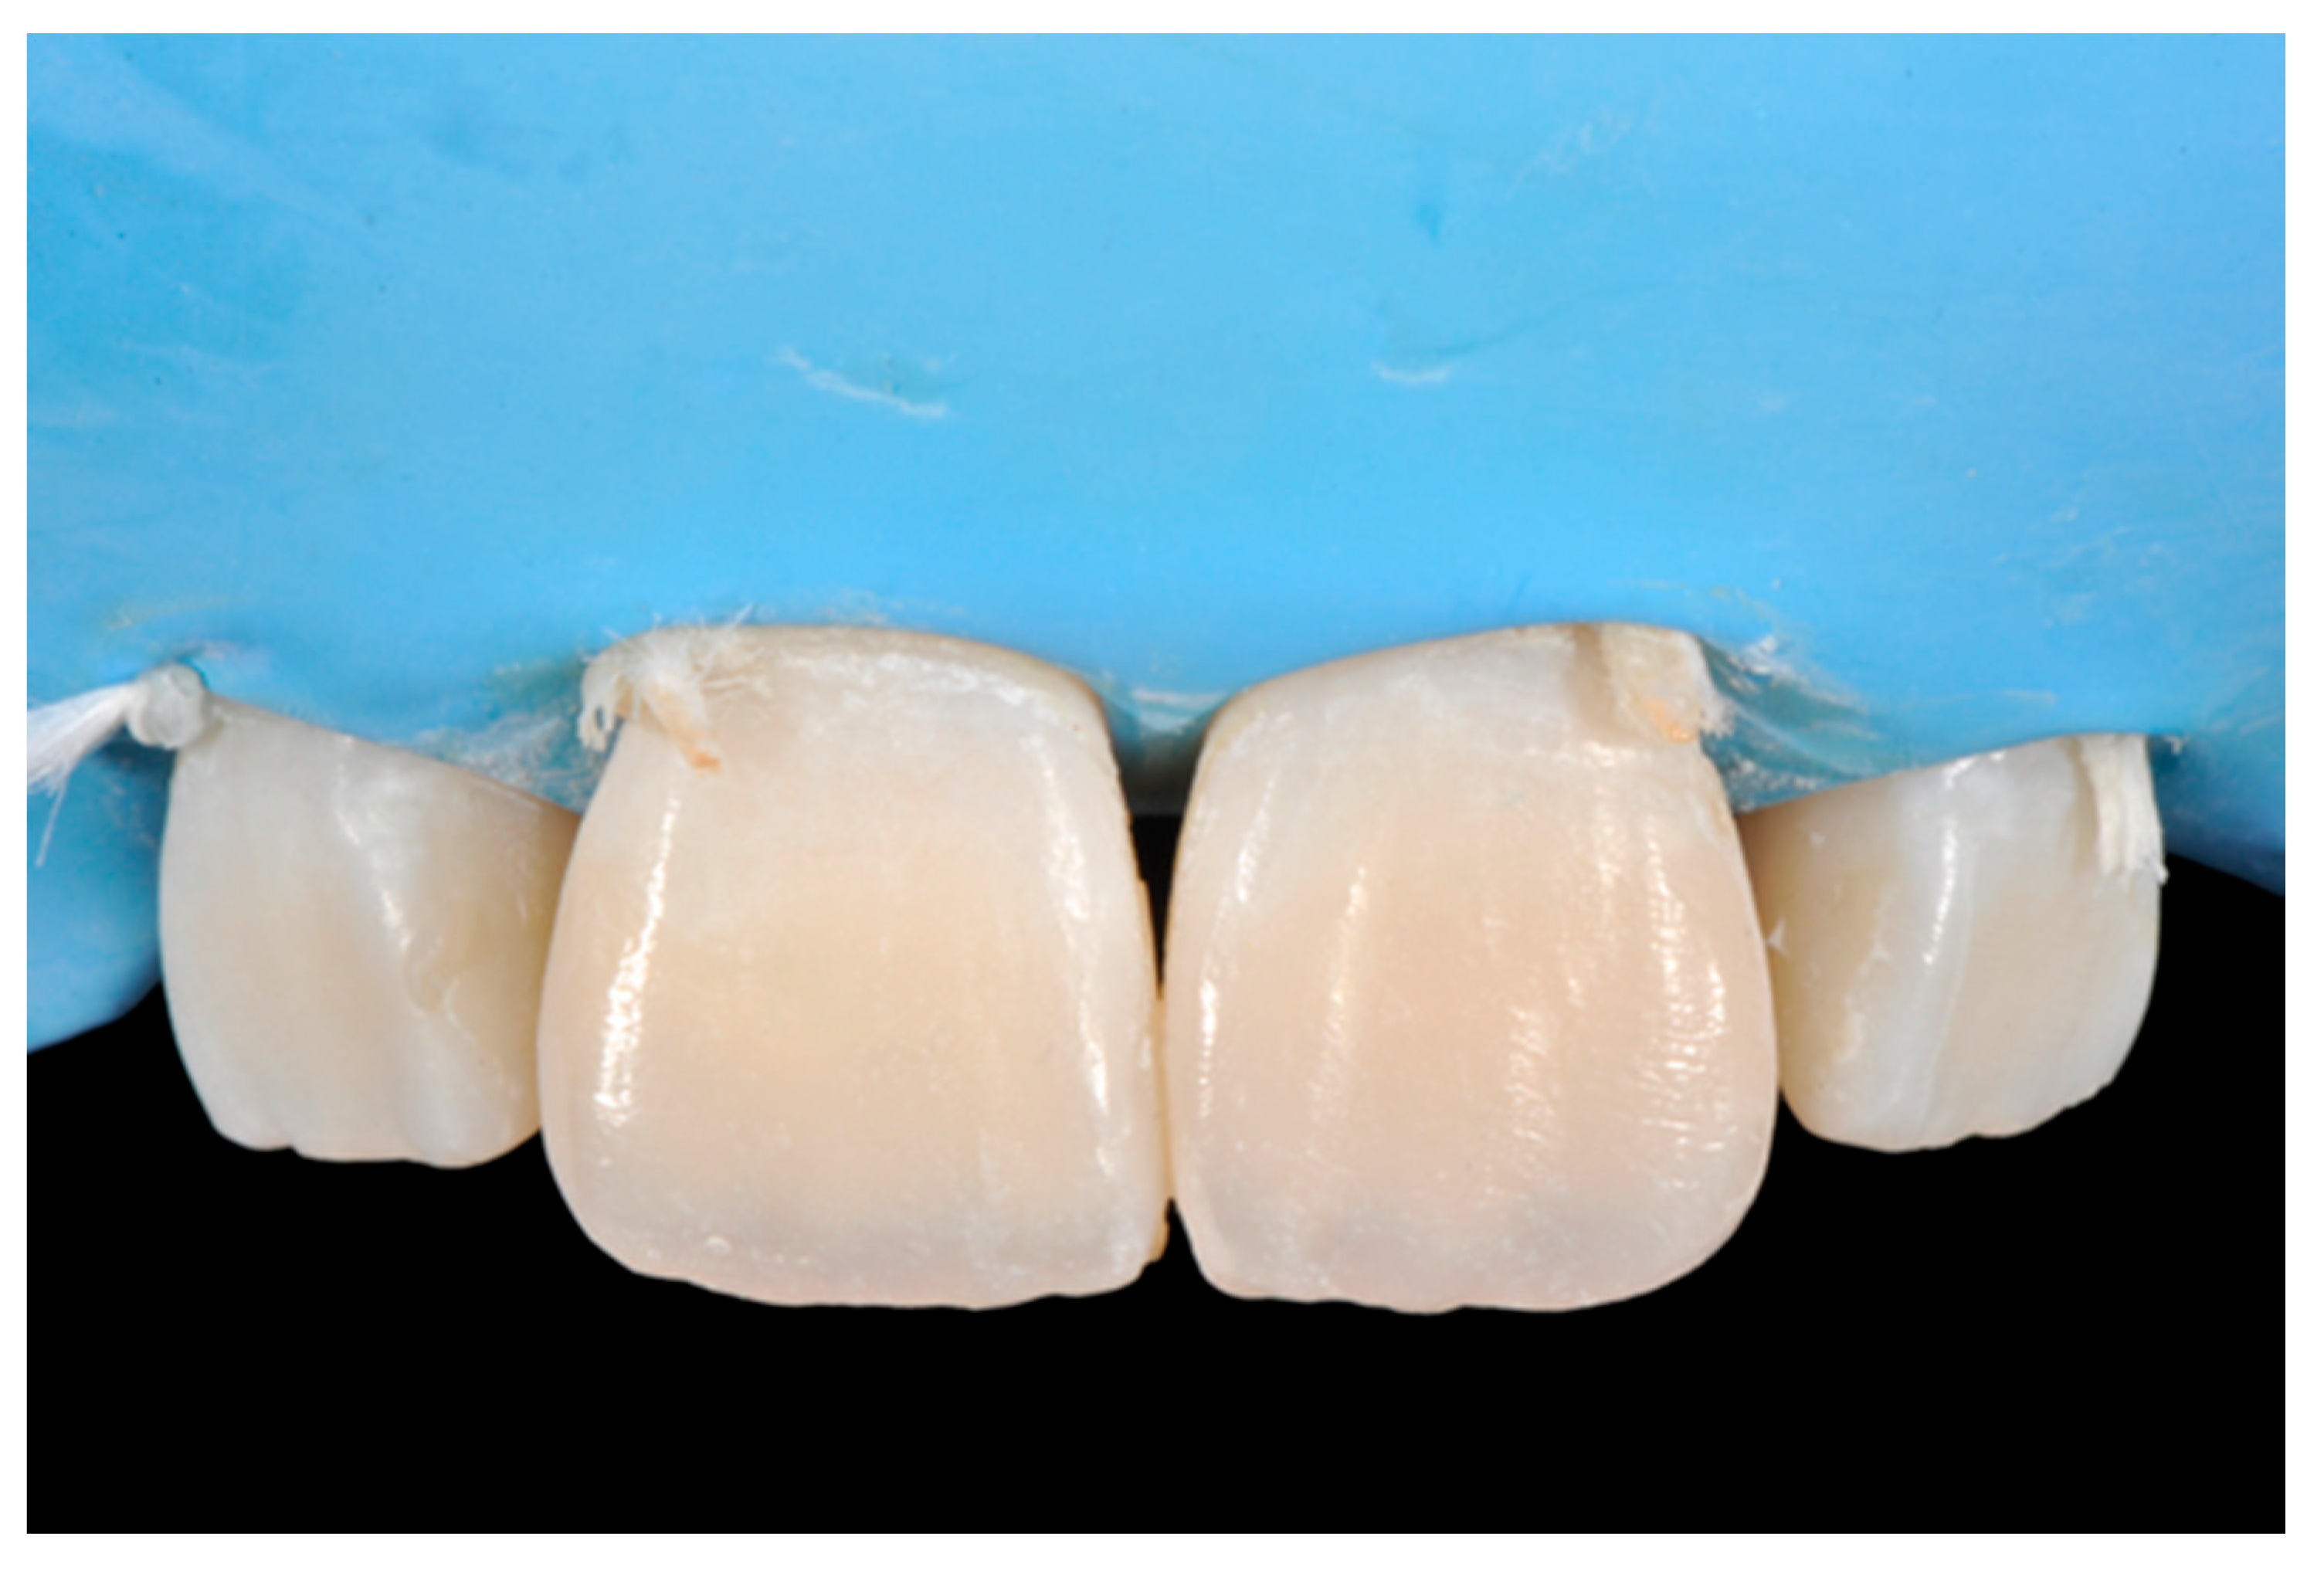

Once completed, the two frames (Clearfil Majesty ES-2, A1E, A2D, Kuraray Noritake Dental, Tokyo, Japan) showed internal and external excesses that were reduced using diamond burs and discs (Figure 33 and Figure 34) strictly following the procedure described in Section 2.1.2 of present article. Excesses were removed from the distal-incisal angle of #2.1 allowing therefore to obtain the desired translucency. After silane application and bonding procedure (Figure 35) as described in Section 2.1.2, restorations were completed (Figure 36 and Figure 37). They both show satisfactory clinical integration 1.5 years post-operative (Figure 38 and Figure 39).

Figure 35.

The modified frames treated with silane coupling agent and adhesive, ready for layering of dentinal body. Reprinted from Restauri diretti nei settori anteriori, G. Paolone, S. Scolavino, © 2021, with permission from Quintessence Publishing Italy.